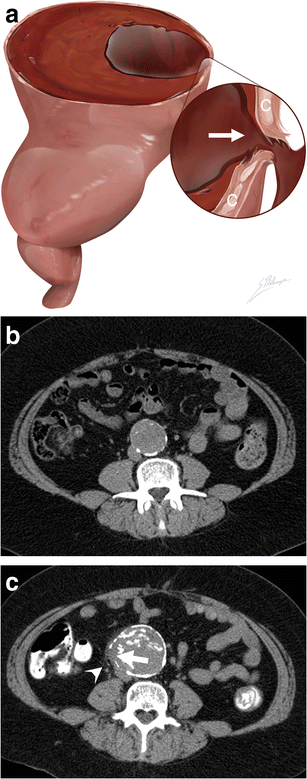

Focal wall discontinuity. a Illustration depicts a focal discontinuity (white arrow) of the calcified intima walls (C), indicating the AAA rupture site. b Axial unenhanced CT image of an asymptomatic 56-year-old man shows a 4.2 cm AAA with intact circumferential calcified walls. c Axial unenhanced CT image of the same patient who presented with severe lumbar pain 4 years later. The AAA now measures 5.7 cm, and a new 1 cm focal gap (white arrow) of the circumferential calcifications can be seen with periaortic fat infiltration near the rupture site (white arrowhead)